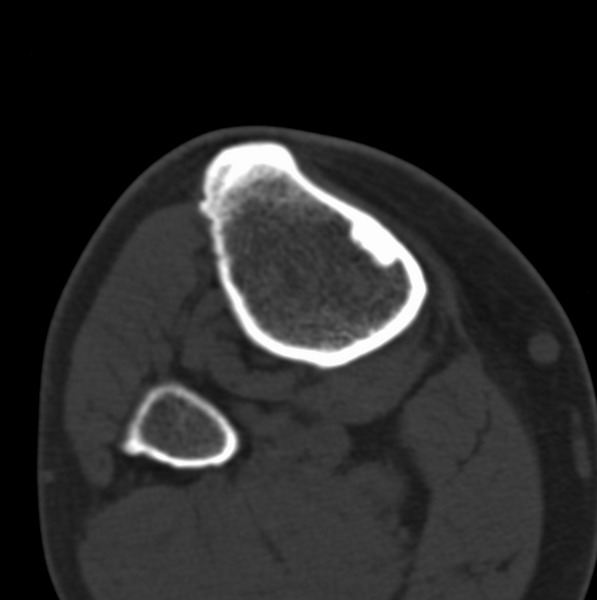

右侧膝关节疼痛一月

男、48

股骨下段、胫骨上段。

1、股骨干骺端病变考虑干骺端纤维性皮质缺损愈后(非骨化性纤维瘤)改变,胫骨近端内生骨瘤(或干骺端纤维性皮质缺损愈后改变);

2、骨关节炎,骨质增生,股骨外侧髁退变性囊肿(关节面软骨下囊肿);

股骨干骺端病变考虑非骨化性纤维瘤。

1、股骨干骺端病变考虑干骺端纤维性皮质缺损愈后(非骨化性纤维瘤)改变,胫骨近端内生骨瘤;